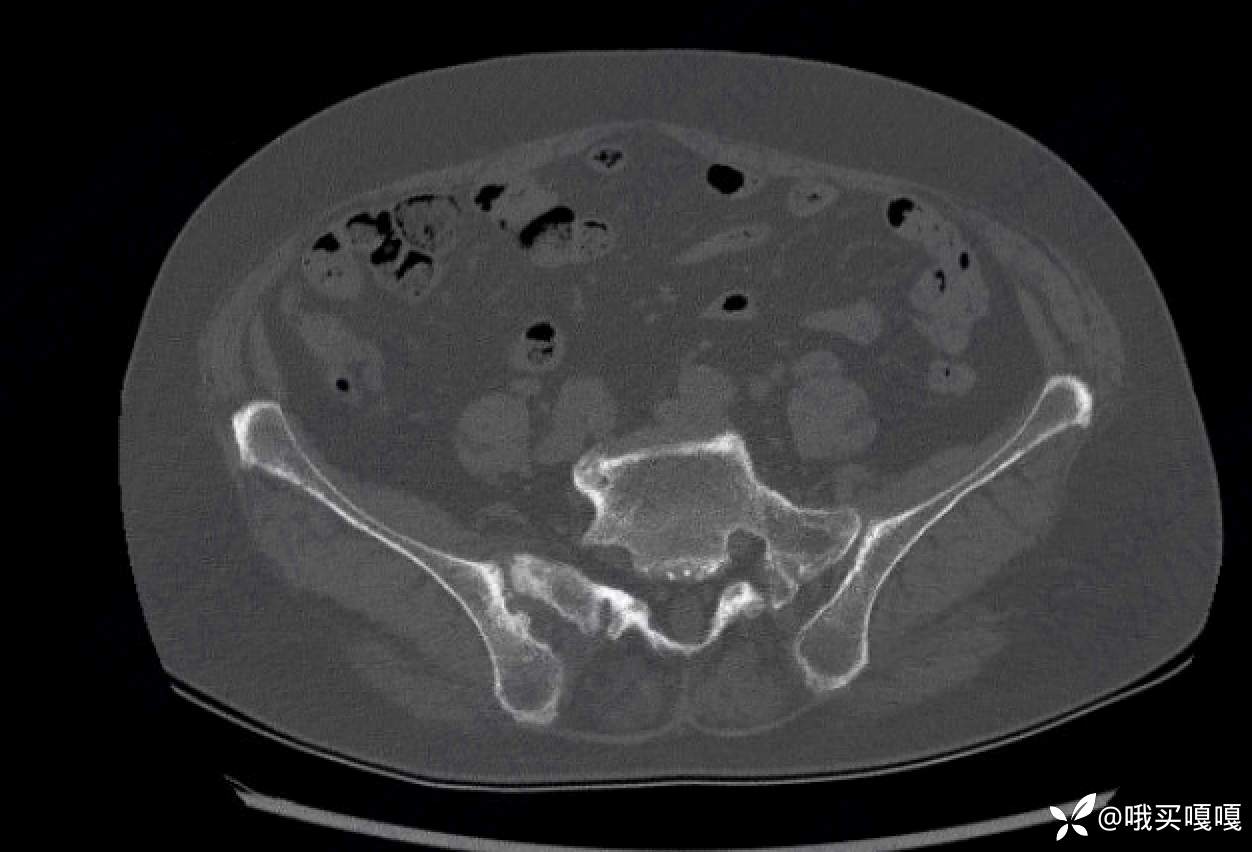

请问各位,这个骶髂关节的CT,看起来像脊柱关节炎引起骶髂关节炎的影像学改变吗?